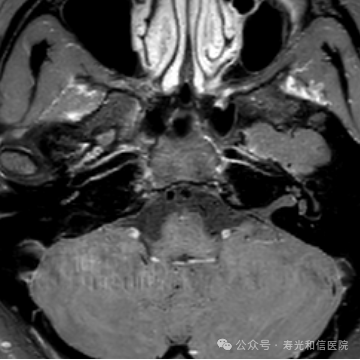

肿瘤治疗(如化疗、靶向治疗)后,若治疗有效,肿瘤细胞密度会降低,水分子扩散能力增强。通过DWIBS定量参数(如ADC值)的变化,医生能更早评估治疗效果。

(肝癌术后发现小转移灶)